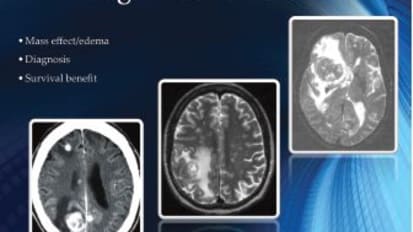

Clinical Minutes: Microsurgical and Radiosurgical Treatment of Metastatic Tumors

George J. Counelis, MD, Medical Director of the Brain Tumor & Neuro-Oncology Program, discusses the technology available within the department's Radiosurgery program - allowing precise treatment for cancer patients.

This white paper explores the treatment of brain and spinal cord cancer which is dependent on the on the tumor’s size, location, and type, as well as the patient’s age and general health.

One of the most highly specialized capabilities offered by John Muir Health’s comprehensive Brain Tumor & Neuro-Oncology program is stereotactic radiosurgery, (SRS) and stereotactic body radiotherapy (SBRT).